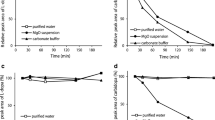

The stability of d-phenylglycine-l-dopa in the intestine was determined prior to the intestinal absorption studies. In order to simulate intestinal microclimate pH, the compound was incubated with the intestinal mucosal suspension in a pH 6.5 isotonic buffer solution. l-Gly-l-Phe comprising essential amino acids degraded rapidly with only 50% of recovery after 2 min of incubation. d-Phenylglycine-l-dopa, on the other hand, was very stable with almost 100% of recovery after 90 min of incubation (Figure 3).

Comparison of the stability of d -phenylglycine- l- dopa and l -Gly- l -Phe in rat intestinal mucosa suspension. Each point represents mean ± SE. of 3 experiments. A methanolic solution (100 μl) of the test compound (1 mg/ml) was diluted with an isotonic mannitol buffer solution (pH 6.5, 2.4 ml) as the stock solution. This stock solution (1 ml) was mixed with the freshly prepared mucosal suspension (1 ml). The mixture was incubated in a water bath at 37°C and subjected to sampling at intervals between zero to 90 min of incubation. Each sampled solution (200 μl) was denatured with 0.8 ml of MeOH and centrifuged at 6,600 g for 5 min. Each of the supernatant (20 - 100 μl) was subjected to HPLC assay.

The mean plasma concentration-time profiles after single dose oral and i.v. administration of d-phenylglycine-l-dopa and l-dopa are depicted in Figure 4. The pharmacokinetic parameters calculated with the data of plasma concentration-time curves based on the non-compartmental model analysis were summarized in Table 2. The fraction of oral absorption (BA) was calculated according to Equation 1. The Striatal dopamine level after i.v. injection of d-phenylglycine-l-dopa (50 mg/kg) is depicted in Figure 5.

Plasma concentration-time profile of d -phenyglycine- l -dopa (a), (b) and l -dopa (c), (d) after i.v. (a), (c) and oral (b), (d) administration in Wistar rats (n = 6). The aqueous solution of test compound with dose equivalent to 5.97 mg/kg body weight of l-dopa was administered either intravenously from the tail vein or orally by a feeding tube. Blood samples were collected from the carotid artery at time intervals of from 1 to 180 min. Heparin sodium (25 I.U./ml in 0.3 ml of saline) was added to blood samples, and were then centrifuged at 6,600 g for 5 min. Plasma was stored at -78°C until being analyzed. A 200 μl of the plasma sample in a 10 ml test tube was mixed with 500 μl of 1.0 M Tris buffer (pH 8.6, adjusted by EDTA-2Na+) and 10 μl of 3,4-dihydroxybenzylamine (DHBA, 2 μg/ml) was added as internal standard. Alumina 100 mg was then added and then shake for 15 sec and the supernatant was decanted. The alumina was washed four times with 5 ml of water, and the adsorbed compounds on the alumina was eluted with 200 μl of an acidic solution (0.9 ml of glacial acetic acid in 4.0 ml of 1.0 M phosphate buffer). A 30 μl of the eluent was then analyzed by HPLC.